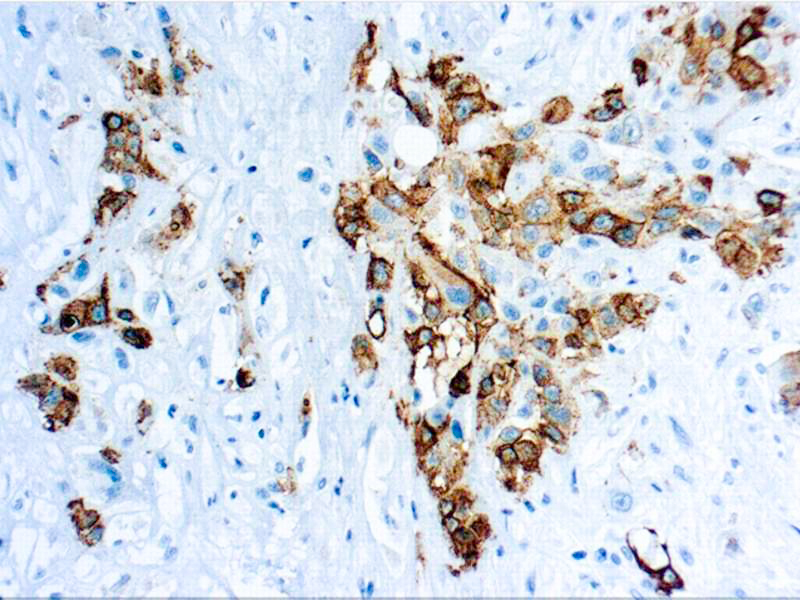

Mesothelin is a glycocylphosphotidylianositol-linked cell-surface glycoprotein, which is present on the surface of normalmesothelium and is overexpressed in many patients with epithelial ovarian cancer and malignantmesotheliomas.

| Positive Control Tissue | Mesothelioma |